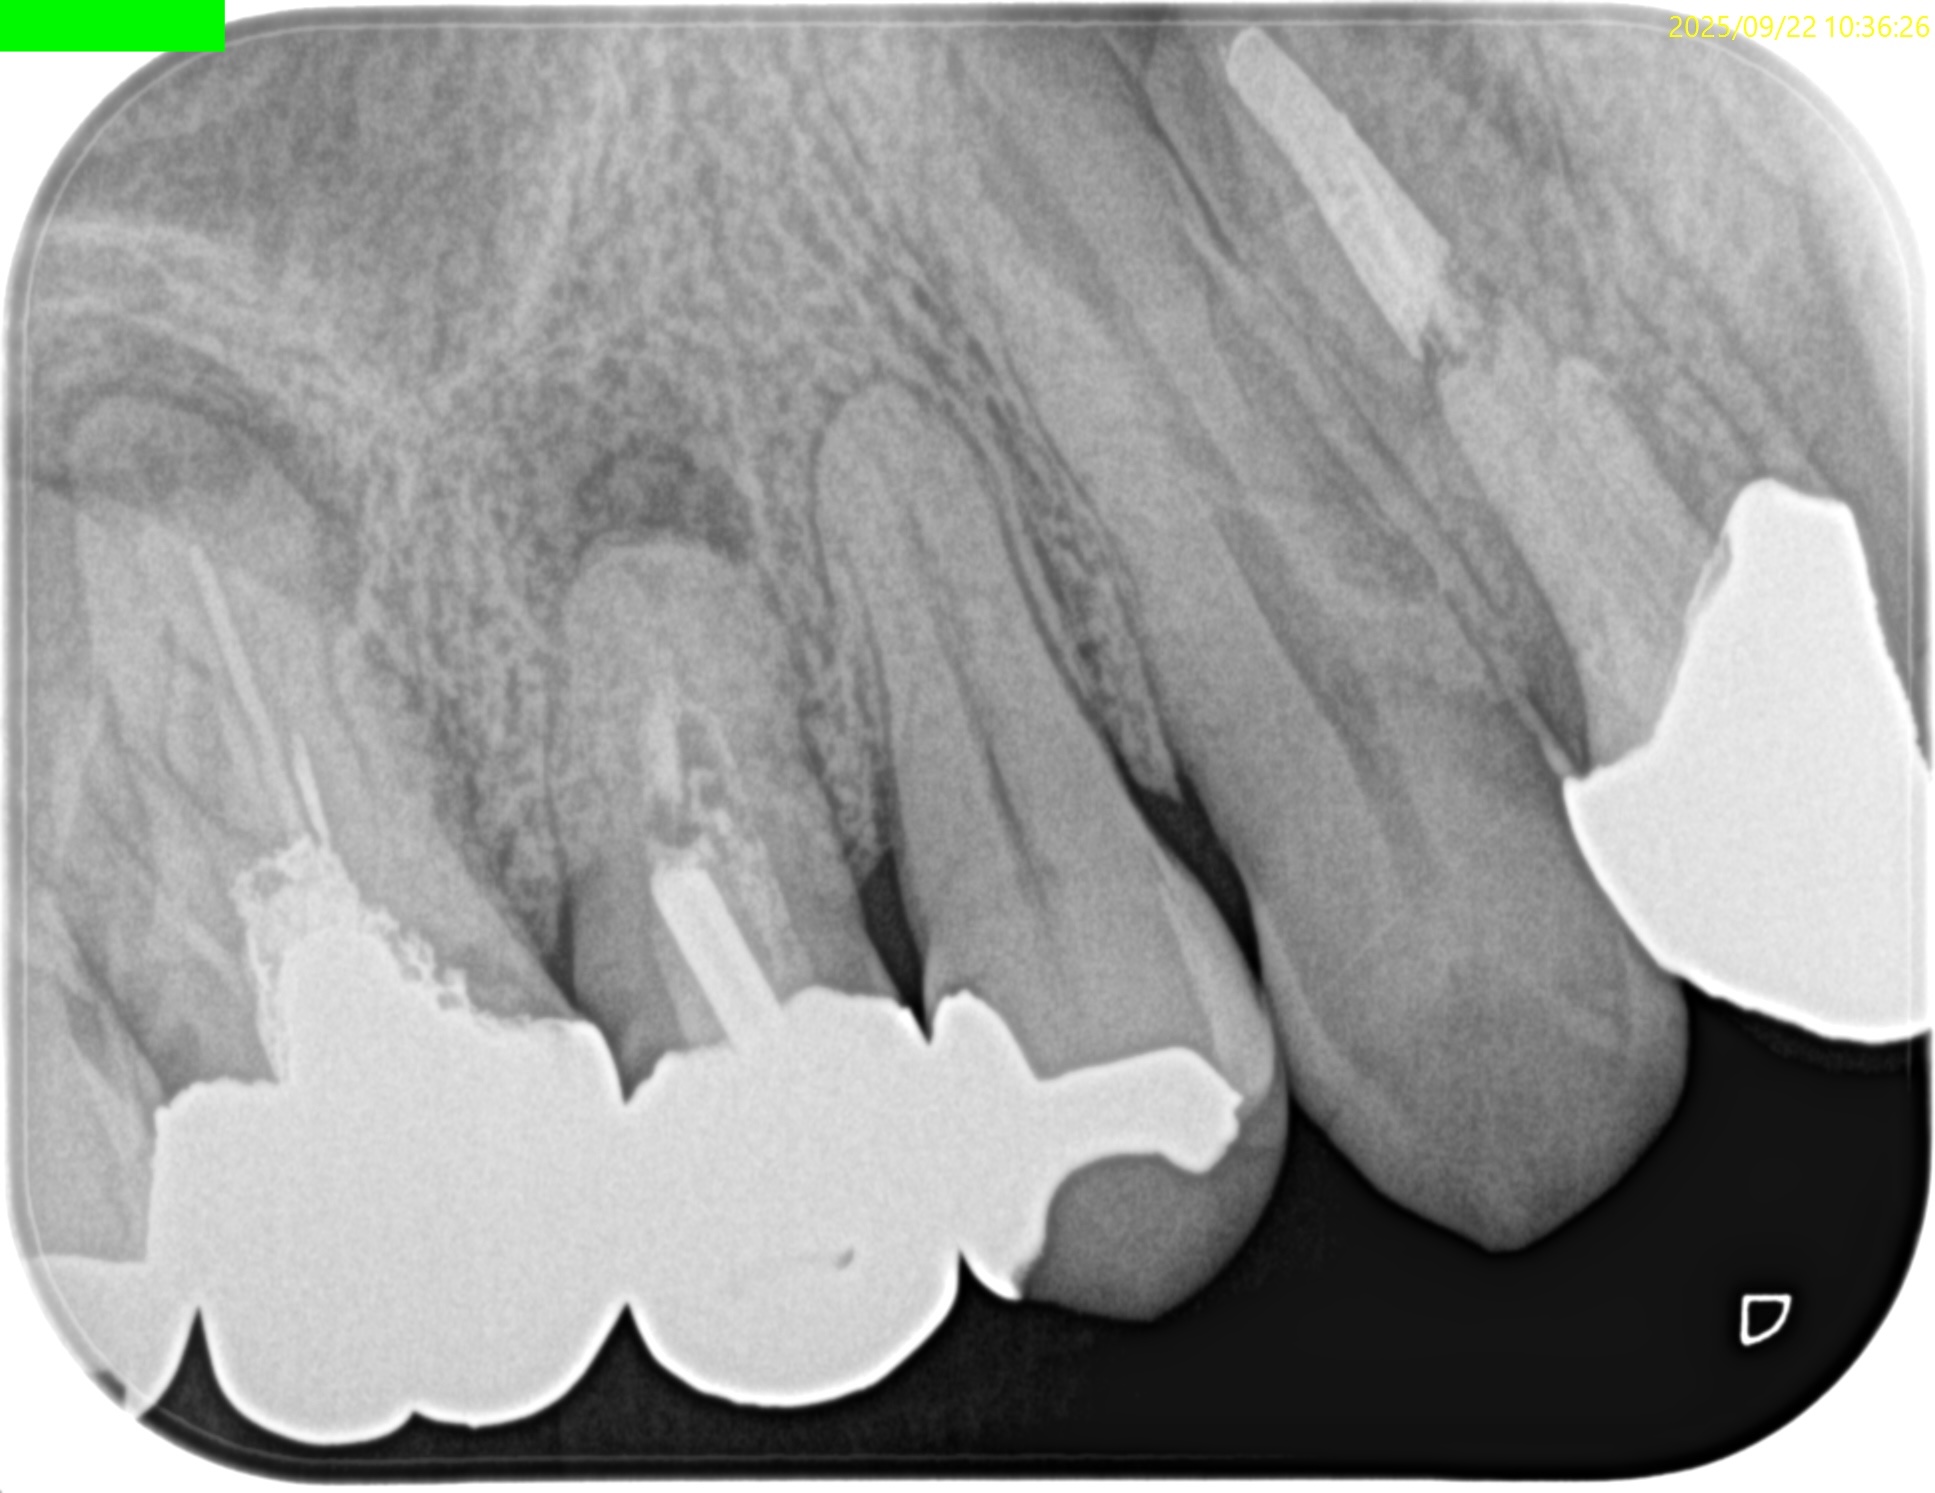

術後にPA, CBCTを撮影した。

#60.04で問題はなかった。

このように現代の歯内療法は、

Gutta Percha Pointの試適との戦い

であるということがわかるだろう。

問題はない。

ということでこの歯の予後は6ヶ月後にCheckする。